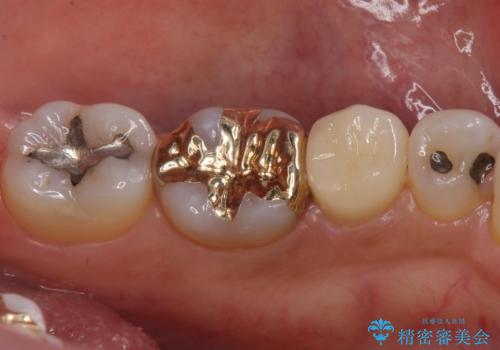

- 左下の奥歯に虫歯がある気がするとのことで来院された患者様です。

手前はジルコニアクラウンで白く、奥はゴールドアンレーでより適合の良いものを装着します。

- 左下5:仮歯 11,000円、ジルコニアクラウン(スタンダード)121,000円 / 左下6:ゴールドアンレー110,000円 合計242,000円費用は治療当時の料金となります